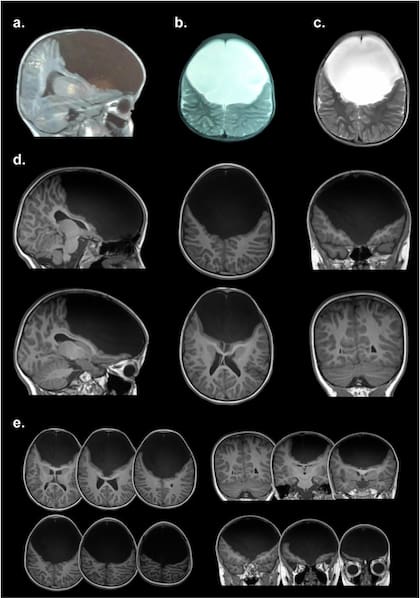

Gabriela iba a una escuela común, hasta que hace unos tres años comenzó a mostrar una conducta desinhibida y era imposible de controlar. Estudios de resonancia magnética y otros exámenes médicos arrojaron un resultado inesperado: por alguna razón que es imposible determinar con precisión a Gabriela le "falta" una gran parte del cerebro que abarca los lóbulos frontales, precisamente las estructuras que son claves para los mecanismos de control y la capacidad de abstracción. Pese a que, como dice su madre, "debería ser un vegetal", Gabriela habla, camina, conoce los colores, es consciente del paso del tiempo. Su caso desafía muchas de las nociones aceptadas por la neurociencia actual. Katherine había oído hablar de Facundo Manes y su equipo de Ineco, y le escribió para pedirle ayuda. Fue así como un grupo de investigadores argentinos viajó a Colombia y pudo estudiar a su hija.

"Se trata de un caso absolutamente excepcional; no existe otro así en la literatura –cuenta Agustín Ibáñez, director del Instituto de Neurociencia Cognitiva y Traslacional (Incyt), de triple dependencia: Ineco-Favaloro-Conicet, primer autor del trabajo que lo describe en Neuroimage: Clinical, y que también firman Máximo Zimerman, Lucas Sedeño, Nicolás Lori, Melina Rapacioli, Juan Cardon, Diana Suárez, Eduar Herrera, Adolfo García y Facundo Manes (doi.org/10.1016/j.nicl.2018.02.026)–. Cuando vi las resonancias, pensé que no caminaba, porque no tiene corteza motora, que no hablaba, porque carece de las áreas de Broca, que no sentía, porque tampoco tiene las ínsulas anteriores..."

Para los investigadores, la afectación de la corteza frontal debe haber ocurrido entre la semana 20 y 30 de la gestación, y eso le dio al cerebro la oportunidad de expresar su increíble capacidad de reorganización. "De hecho, todos los ‘cables’ que se deberían conectar con estructuras frontales van hacia atrás –destaca Ibáñez–. Si una neurona tiene que conectarse con algo en el frente que no contesta, se va para otro lado. Esta reorganización atípica explicaría cómo esta chica puede hablar sin tener área de Broca, cómo puede caminar sin una corteza motora".

Mediante el análisis de los tractos cerebrales y la conectividad funcional, los investigadores pudieron observar esta modificación excepcional de las conexiones de su cerebro. Precisamente, para Facundo Manes este estudio muestra cómo las neurociencias cognitivas contemporáneas pueden ayudar a comprender la reorganización cerebral; y por qué este caso presenta tanta preservación de funciones cognitivas.

Entre las posibles causas de lo que le ocurre a Gabriela, los investigadores barajan que podría deberse a un quiste con líquido cerebroespinal que gradualmente haya desplazado los lóbulos frontales; a causas genéticas; o a que se haya producido un quiste de células aracnoides y colágeno. "Uno no se explica cómo no hay una comprensión extrema del cerebro –afirma Ibáñez–. Es un caso muy atípico".